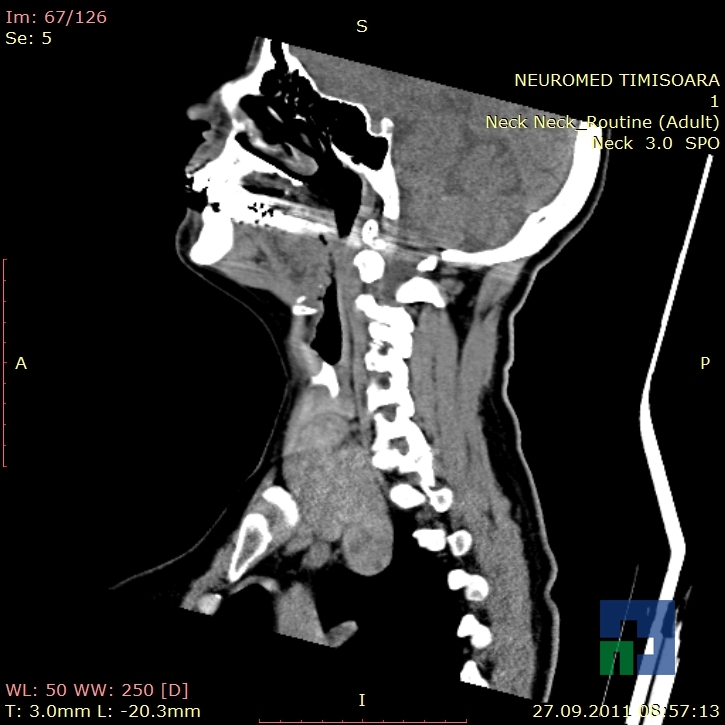

Examinare de rutină cerebrală, nativ și cu substanță de contrast (SDC) pentru diagnosticul:

- Accidentelor vasculare cerebrale ischemice sau hemoragice

În cazul traumatismelor cranio-cerebrale:

- Evaluarea deplasării liniei mediane

- Evaluarea cisternelor perimezencefalice

- Diagnosticul edemului cerebral, a contuziei cerebrale, a leziunilor axonale difuze edematoase/hemoragice, a dilacerării cerebrale, a hematomului intraparenchimatos posttraumatic, a hematoamelor subdurale/extradurale (acute, subacute, cronice), a hemoragiei intraventriculare, a hemoragiei subarahnoidiene

- Diagnosticul traumatismelor de bază de craniu

- Diagnosticul fistulei LCR